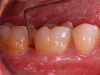

Clinical PPD is measured to the nearest millimeter by means of a graduated periodontal probe with a standardized tip diameter of approximately 0.4 mm to 0.5 mm. Several factors can influence the measurements made with periodontal probes, including: the thickness of the probe used5; the angulation and positioning of the probe depending on anatomic features, such as the contour of the tooth surface (Figure 1 through Figure 3)6; the graduation scale of the probe5; the pressure applied on the instrument during probing6; and the degree of inflammatory cell infiltration in the soft tissue and accompanying loss of collagen.7

Fig 1. Inaccurate probing angle wrongly indicates probing depth at 3 mm, which does not correspond to the radiographic finding shown in Fig 2.

Fig 3. Correct angulation of the probe demonstrates 6-mm probing depth.